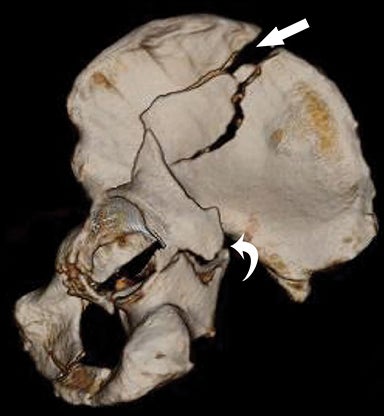

إلا أن التصوير المقطعي CT هو المعيار الذهبي للتشخيص، إذ يحدد نمط الكسر وامتداده بدقة ويُستخدم لتخطيط العلاج الجراحي.

يعتمد التصنيف الأكثر شيوعًا وهو Judet & Letournel على تقسيم الكسور إلى:

1. كسور أولية (Elementary):

كسر كلا العمودين